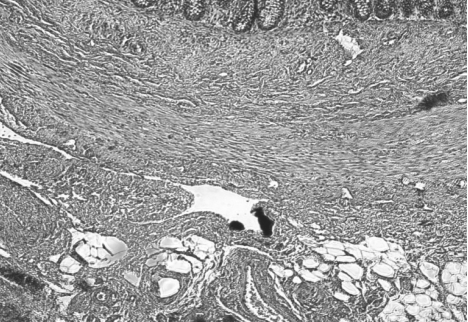

Un'ecografia

addominale conferma un diffuso ispessimento della parete

intestinale e la presenza di una piccola falda ascitica.

(fig.1-2)